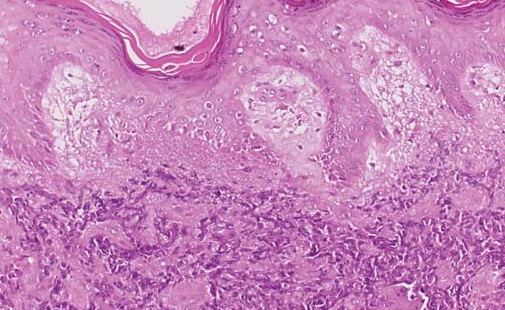

A Caucasian man aged 74 years applied to another urology center for mild lower urinary tract symptoms in 2003. The patient’s PSA was 23 ng/ml. According to the physical examination signs and PSA, he underwent a transrectal ultrasonography guided prostate biopsy. The pathologic examination of the prostate revealed Gleason score: 3+4=7 adenocarcinoma of the prostate. Investigations showed stage T2N0M0 disease and the patient was treated with radiotherapy to pelvic lymph nodes and the prostate. Six years after initial diagnosis, the patient had a complaint of palpable left side 2X2 cm subcutaneous solitary mass, which localized just behind the scapula. The patients’ labarotory tests including serum acid phosphatase and PSA were in normal ranges. General surgery department performed a diagnostic biopsy of the mass and totally excised the lesion. The pathologic examination of the mass showed small cell carcinoma metastasis with chromogranin + and the pathologist advised us to examine the lung or prostate for primary tumour. The patient was undertaken a transrectal ultrasonography guided prostate biopsy and pathologic result revealed small cell carcinoma within residual adenocarcinoma. We investigated the other sites for metastasis and restaging investigations showed 1 cm metastatic lesion in the liver. Medical oncology department decided to treat the patient with combination chemotherapy with etoposide and cisplatin in 6 cycles; but we lost the patient due to disseminated myocardial infarction before starting fifth combination chemotherapy cycle.

Clinicians should keep in mind that early diagnosis of this disease is very difficult due to early metastatic spread of small cell carcinoma and lack of concordant elevation of PSA. There is not any accepted standart treatment modality for this pathology and overall prognosis is poor.

Skin metastasis

Skin metastasis of SCCP